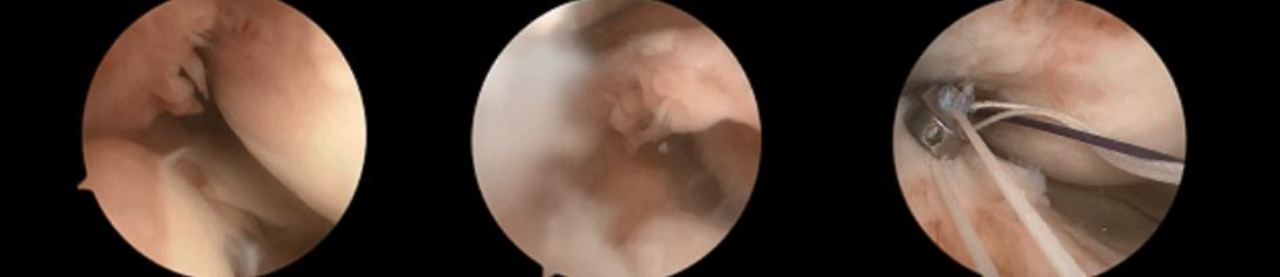

镜下双袢联合高强线“三重固定”

步骤2:插入两条PDS线并引入高强线,分别并将其穿过后交叉韧带,以形成初始的吊带环。

第三步:双套环高强线复位骨折块,并穿入固定微孔钛板。

步骤4:将一根高强度缝合线穿过骨隧道,并牢牢收紧,以准确复位骨折段。

第五步:拉紧双环以稳定骨折部位,并抓住两条牵引缝线。

步骤6:紧固牵引缝线以防止固定环滑脱。